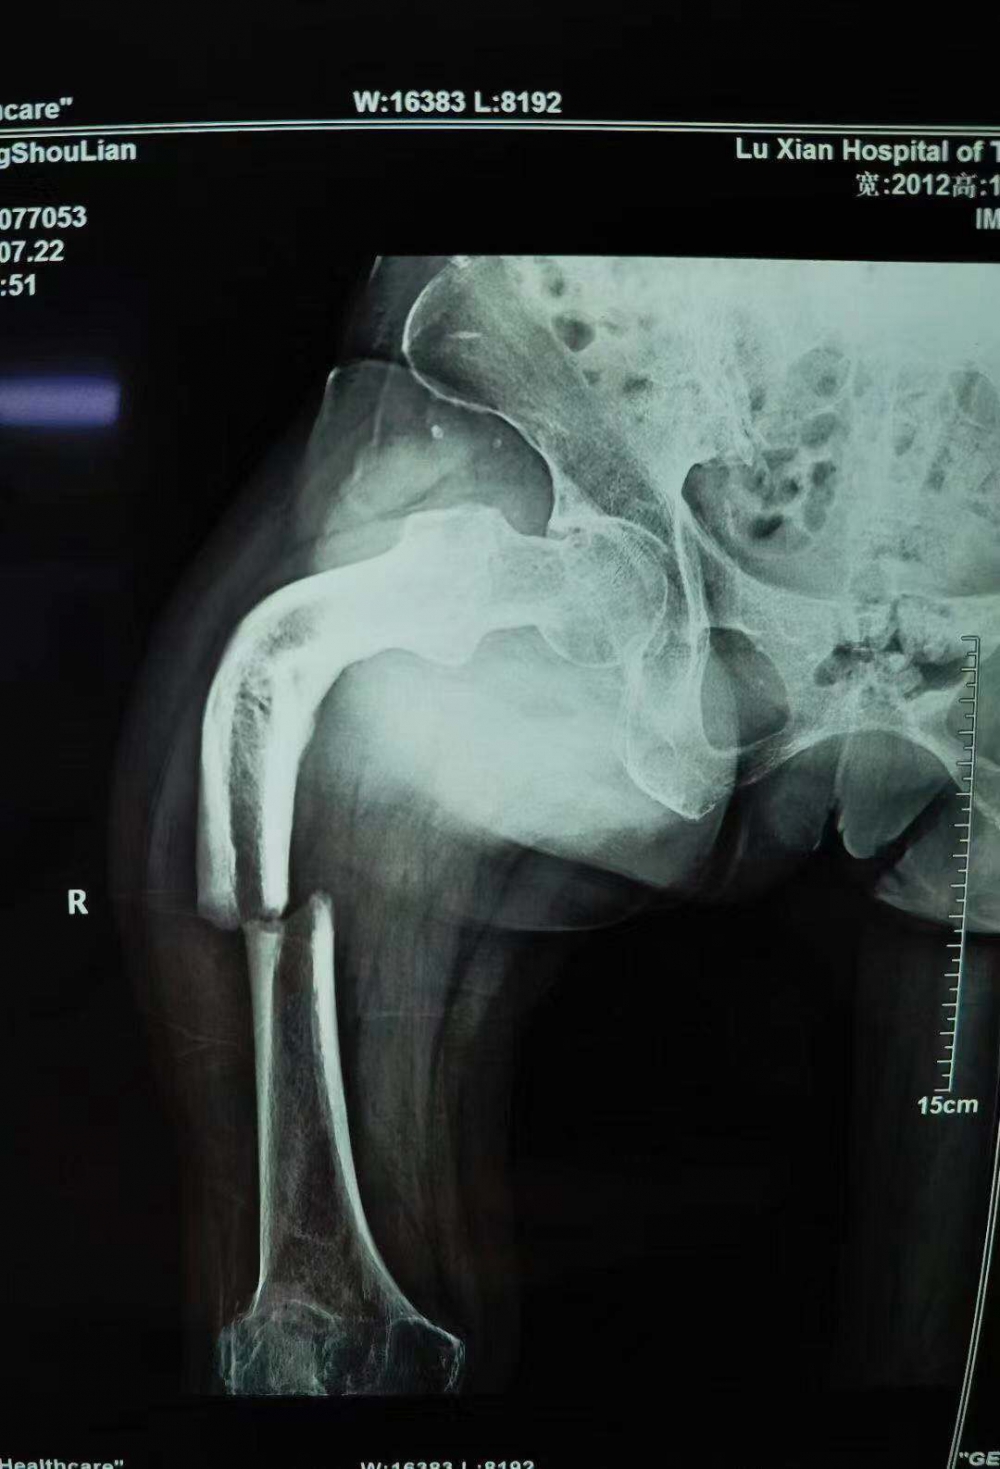

66歲的張守蓮怎么也想不到,她最近在家門口壩子走路時(shí)不小心摔斷了腿,卻因禍得福,把自己三年來(lái)跛足的腿一并醫(yī)治正常了。 (8月9日,張守蓮康復(fù)鍛煉走路) 樹要發(fā)枝,腿也會(huì)發(fā)“新芽”? 張女士家住瀘縣云錦鎮(zhèn),常年在家務(wù)農(nóng)。近日,她在家門口壩子走路時(shí),不小心把大腿摔斷,家人隨即打了120,送到當(dāng)?shù)鼗鶎?..